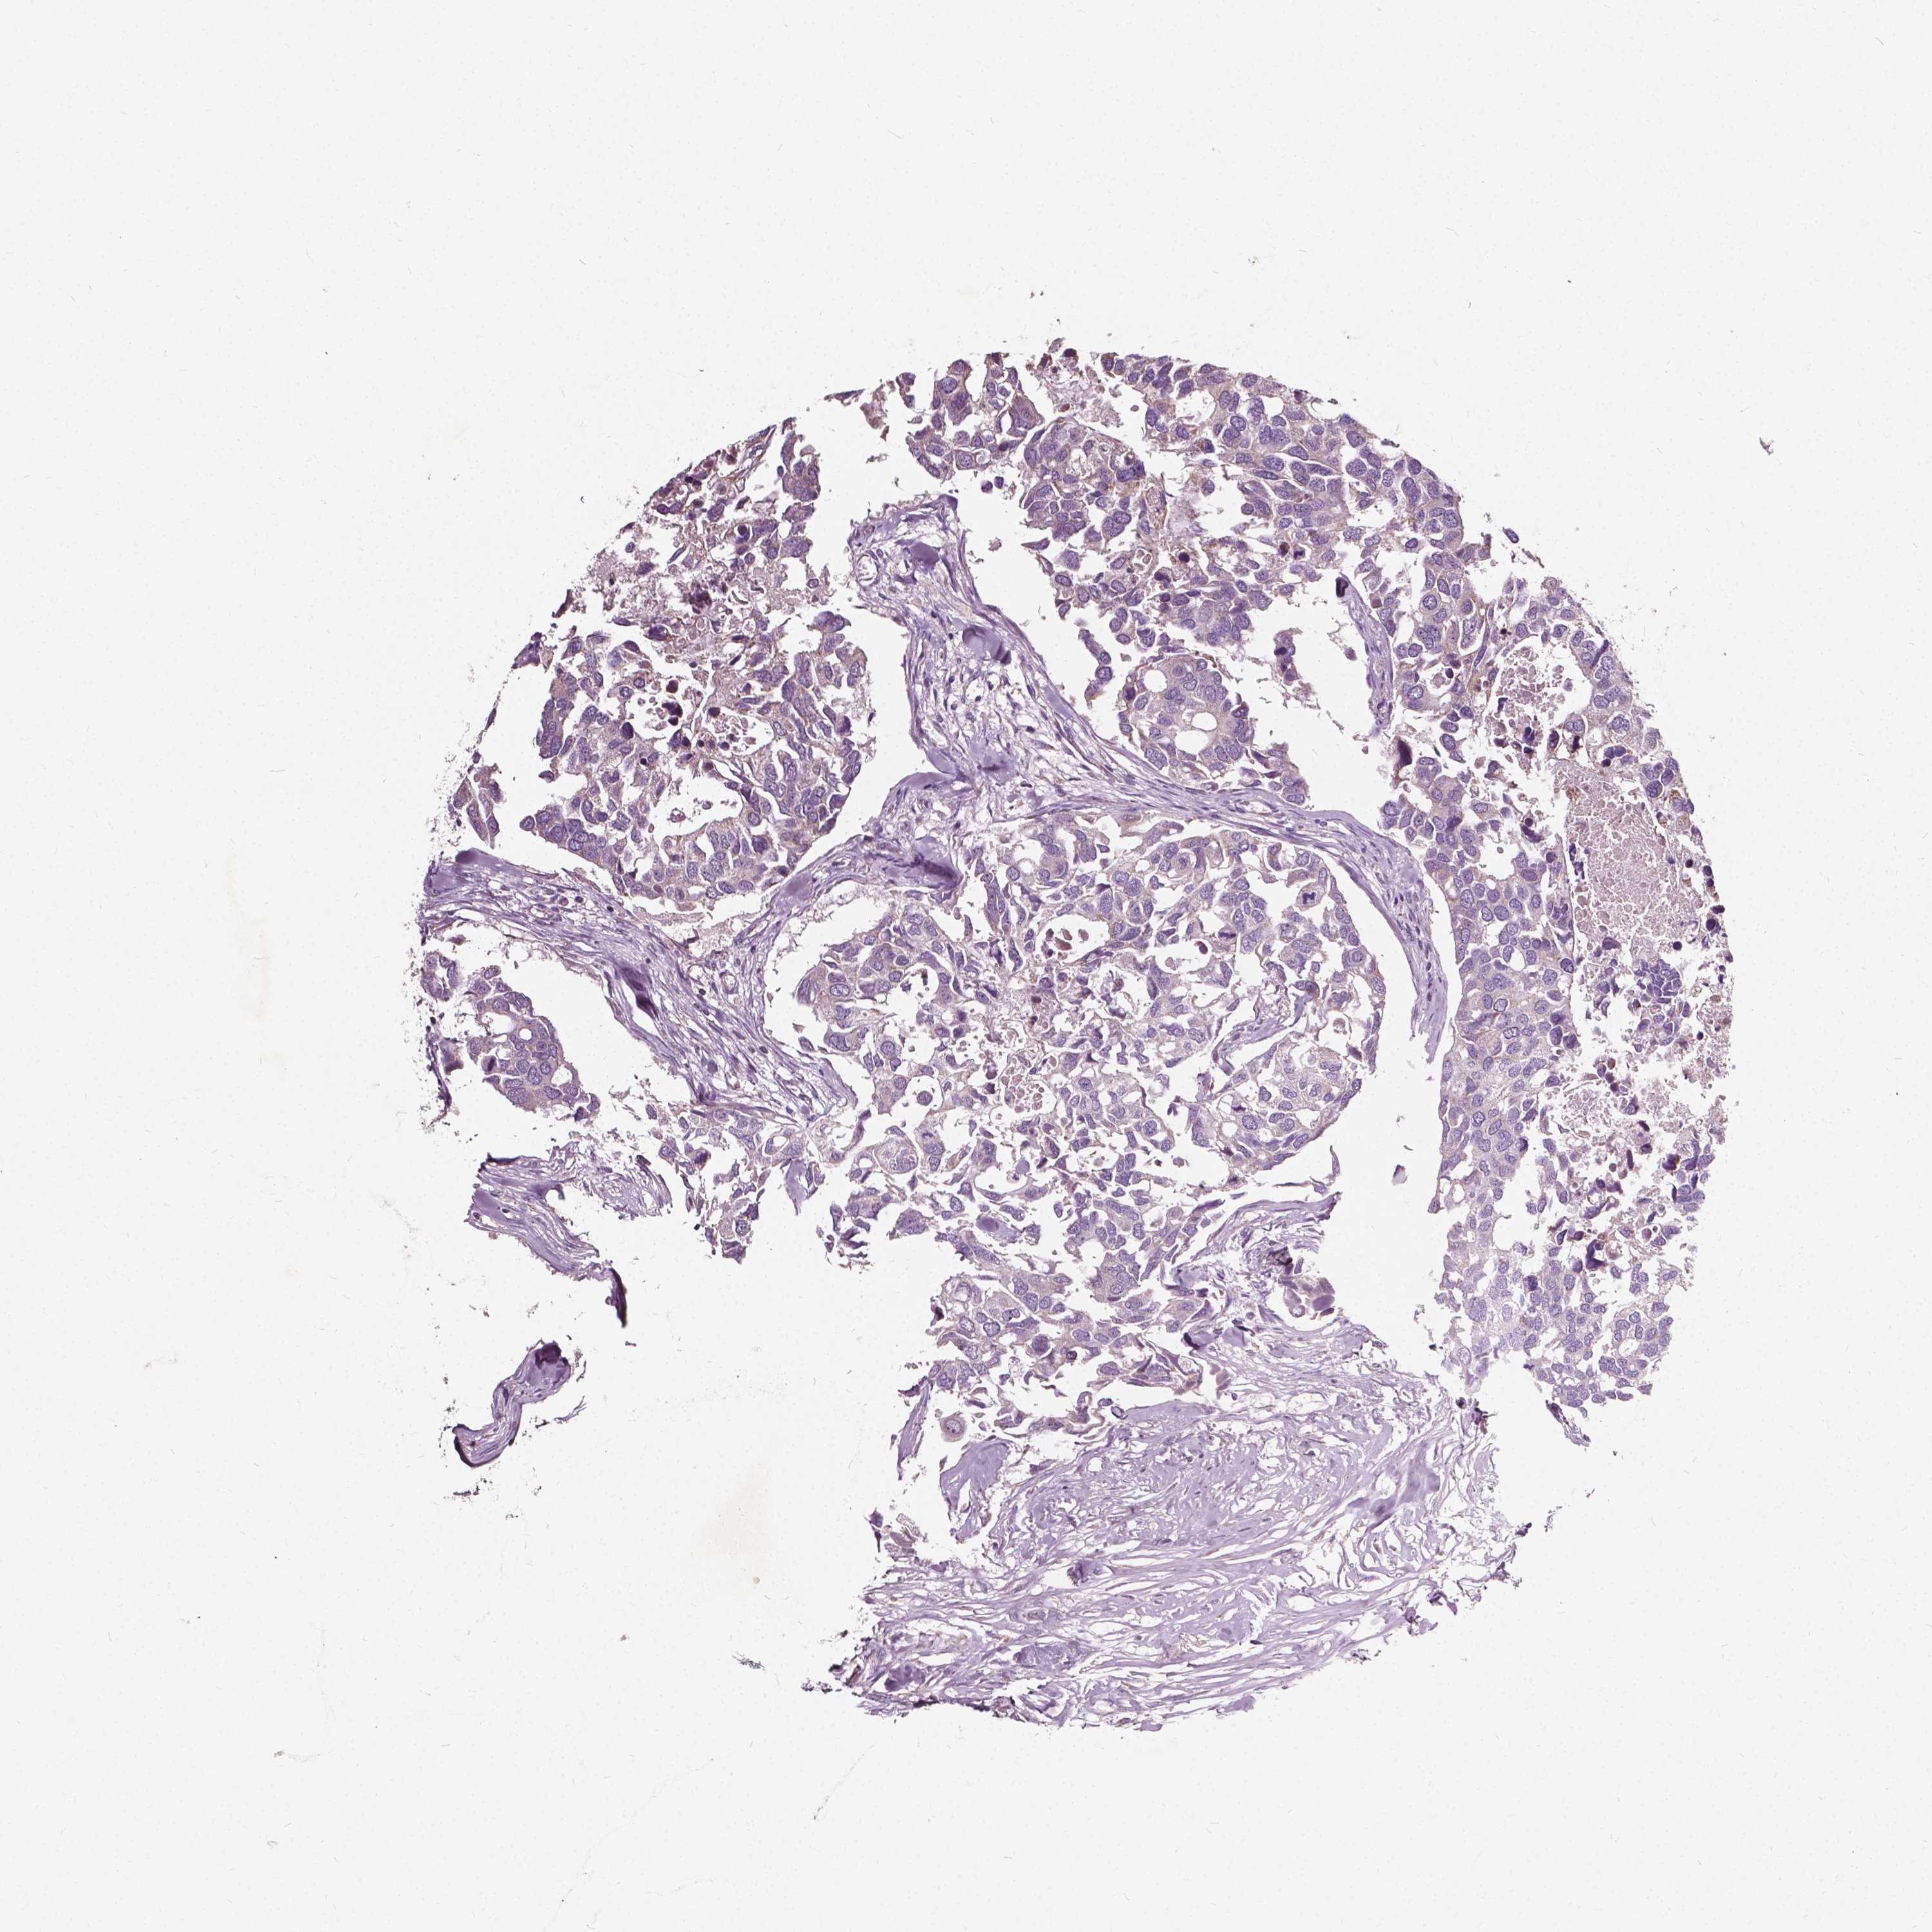

CANCER BREAST CANCER Show tissue menu

BRCA TCGA BRCA VALIDATION PROTEIN EXPRESSION

Breast cancer

Human cancer